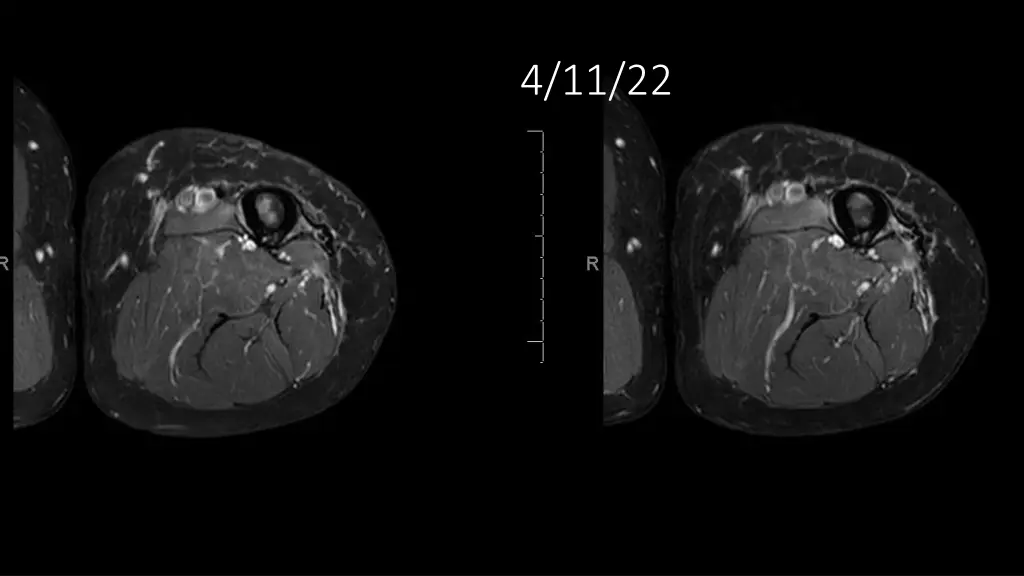

62-year-old shows post-surgery progress from 11/4/2020 to 4/11/22

Explore the journey of a 62-year-old individual post-UPS resection on 11/4/2020, through a series of dated images leading up to 4/11/22. Witness the transformation and recovery process in these visual updates reflecting the progression over time.